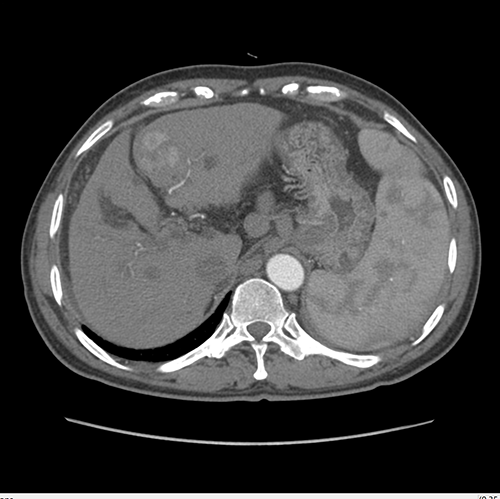

门脉高压、门静脉海绵状变、S3肝癌------S3切除、脾切除